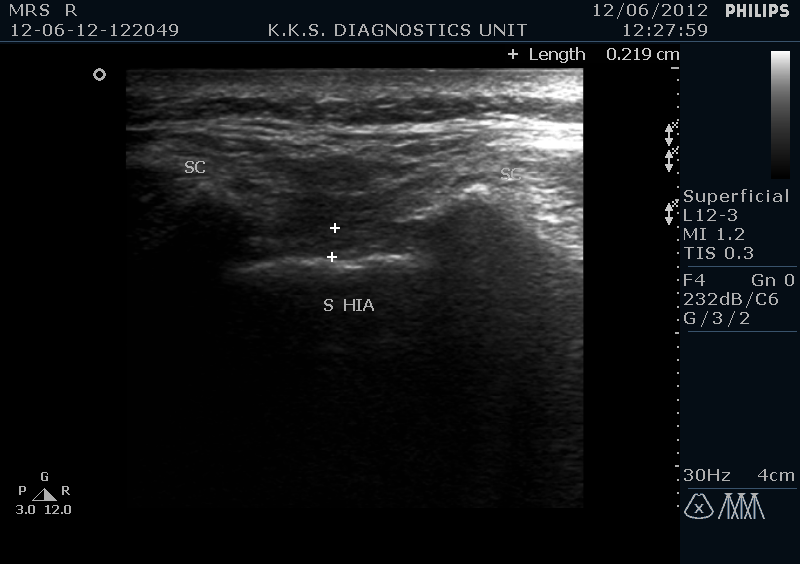

In prone position the scanning is initiated from midline in transverse probe alignment from the median crest of the sacrum which is seen as an echogenic bony prominence .As we proceed caudad from this level we encounter in para-sagittal region bilaterally two convex echogenic shadows with a hypo echoic 2-3mm band running between the two. These are the saccral cornua with saccral hiatus in between . Superior to this configuration, is a hypoechoic band of saccrococcygeal ligament and posteriorly a dense echogenic line of posterior surface of the sacral bone.

In the longitudinal view, sacral hiatus is seen as a darkish hypoechoic beak like structure which is enclosed between the sacrococcygeal ligament superiorly and sacral bone inferiorly.

Sonograhic Long. View sacral hiatus Tr. View sacral hiatus with sacral cornu

Ultrasound probe with frequency range between 12-7 MHz is placed transversely at the level of the sacral dip in midline for the location of the sacral hiatus. Sacral cornu are sonographically important landmarks and the space of few millimeters between the two, seen transversely as hypoechoic region, is the sacral hiatus.

At this level the transducer is then rotated longitudinally and the relatively echogenic band superior to the is hiatus is the sacrococcygeal ligament and the inferior echogenic line is formed by the posterior cortical surface of the sacral bone.